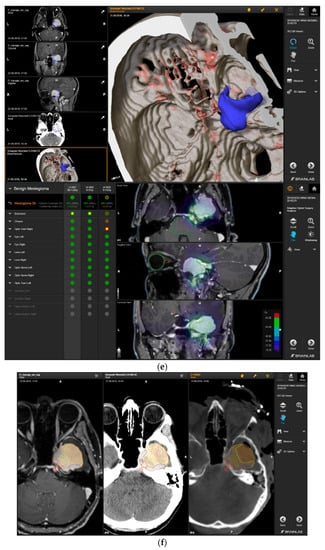

A 58-year-old female presented with progressive headache, difficulty swallowing, diplopia, hearing loss, and reduced face sensitivity on the right side (Figure 4). Elective craniotomy and AHSA-assisted tumor resection were performed. The patient underwent hypofractionated radiosurgery (5 × 5 Gy) of the residual meningioma one year after tumor resection.

Figure 4.

Second representative case of AHSA-supported tumor resection. (a) MRI imaging of petroclival meningioma (axial, coronal, sagittal). (b) Depiction of preoperative tumor volume (orange) and planned residual tumor volume (red). (c) AHSA summary table showing the stereotactic radiation constraints for the preoperatively planned residual tumor volume. With this plan, conventional fractionation and hypofractionation were feasible with effective tumor coverage.

—brainstem: mean dose is safe, while the max. dose is marginally safe;

—right optic tract: mean dose unsafe, max. dose is marginally safe;

—right hippocampus: marginally safe, and mean dose unsafe, max. dose is marginally safe. (d) First intraoperative structure update (ISU) with a residual tumor volume of 82% with the calculated dose constraints for conventional and hypofractionated radiotherapy. Single dose stereotactic radiosurgery was not feasible with this degree of remaining tumor. At this point, the dose constraints for conventional radiotherapy were:

—brainstem: mean dose is safe, max. dose is marginally safe;

—right hippocampus: mean dose unsafe, max. dose is marginally safe. Hypofractionated radiotherapy:

—brainstem: marginally safe;

—right cochlea: mean dose unsafe, max. dose safe;

—right hippocampus: mean dose unsafe, max. dose is marginally safe. (e) Second intraoperative ISU with residual tumor volume of 74% and calculated dose constraints for hypofractionated radiotherapy. Single dose stereotactic radiosurgery was still not considered feasible with this residual tumor volume. The dose constraints for organs at risk for conventional and hypofractionated radiotherapy were unchanged compared to the first ISU. (f) Third intraoperative ISU with residual tumor volume of 47% and calculated dose constraints for conventional, hypofractionated radiotherapy, and radiosurgery. The current dose constraints for organs at risk were the following for conventional radiation:

—right hippocampus: mean dose unsafe, max. dose is marginally safe. Hypofractionated radiation, which was unchanged for the first and second ISU:

—right hippocampus: mean dose unsafe, max. dose is marginally safe. For single fraction radiosurgery, the OAR dose constraints were available but considered to be unsafe.

—brainstem: mean dose unsafe, max. dose safe;

—chiasma: unsafe;

—right cochlea: unsafe;

—left optic tract: mean dose unsafe, max. dose safe;

—right optic tract: unsafe;

—right hippocampus: unsafe. (g) Overlay of preoperatively estimated and intraoperative effective residual tumor volume in AHSA. (h) Final intraoperative dose constraints after last ISU and data fusion with intraoperative CT. The dose constraints for OARs appeared to improve and were as follows for conventional and hypofractionated radiotherapy:

—brainstem: mean dose is safe, max. dose is marginally safe.

—brainstem: mean dose safe, max. dose unsafe;

—chiasm: mean dose unsafe, max. dose safe;

—right optic tract: mean dose unsafe, max. dose safe. (i) Comparison of pre- and 3 months postoperative MRI for stereotactic radiation planning. The residual tumor was finally treated with hypofractionated radiotherapy (5 × 5 Gy).